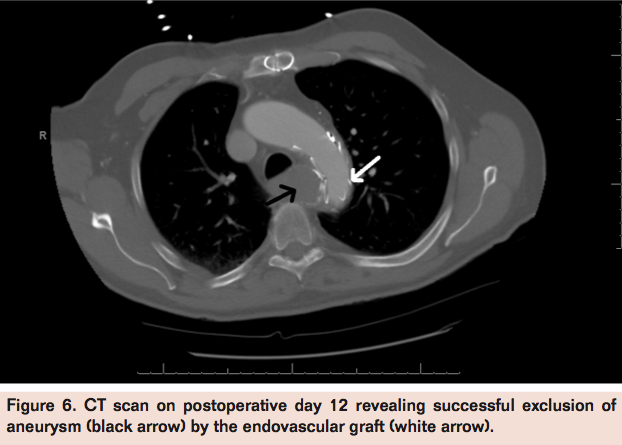

The patient presented postoperatively with another episode of hemoptysis on postoperative day 12. He was otherwise asymptomatic and hemodynamically stable with unremarkable physical examination. Bronchoscopy revealed necrotic residues with no active bleed. CT angiography revealed adequate graft position with aneurysm exclusion. Hemoptysis resolved and patient continued to do well upon 4 months follow-up. Since there are no guidelines upon follow-up, patient was seen 1 month and 4 months postoperatively, and will be seen at 6-month intervals thereafter for a repeat CT scan and a physical exam.